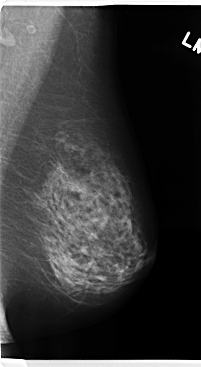

C_0224_1.LEFT_MLO

LEFT_MLO LINES 4760 PIXELS_PER_LINE 2608 BITS_PER_PIXEL 12 RESOLUTION 50 NON_OVERLAY